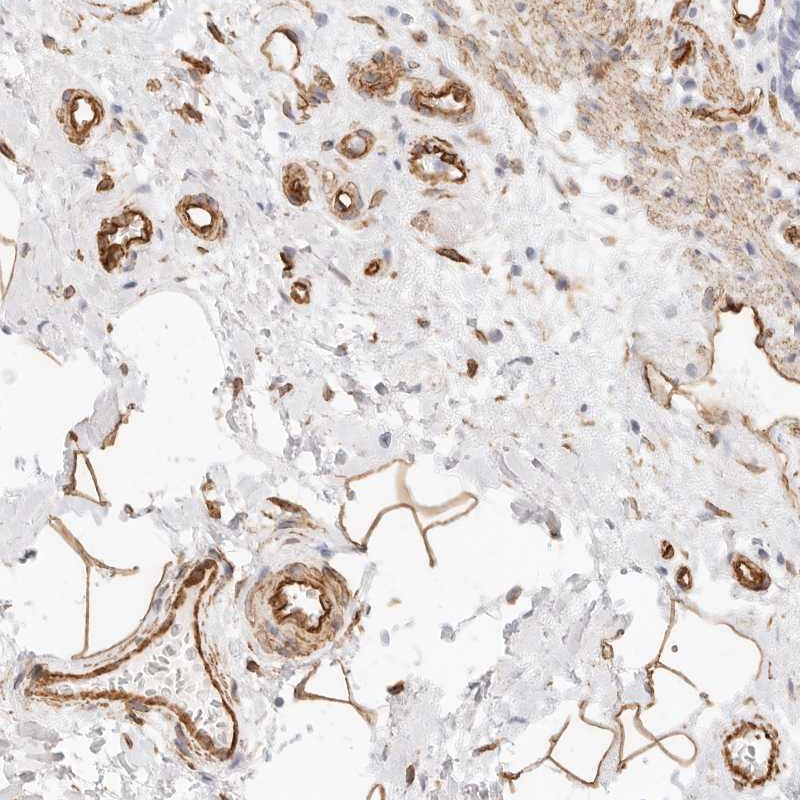

Immunohistochemical staining of human rectum shows distinct positivity in blood vessels and adipocytes.